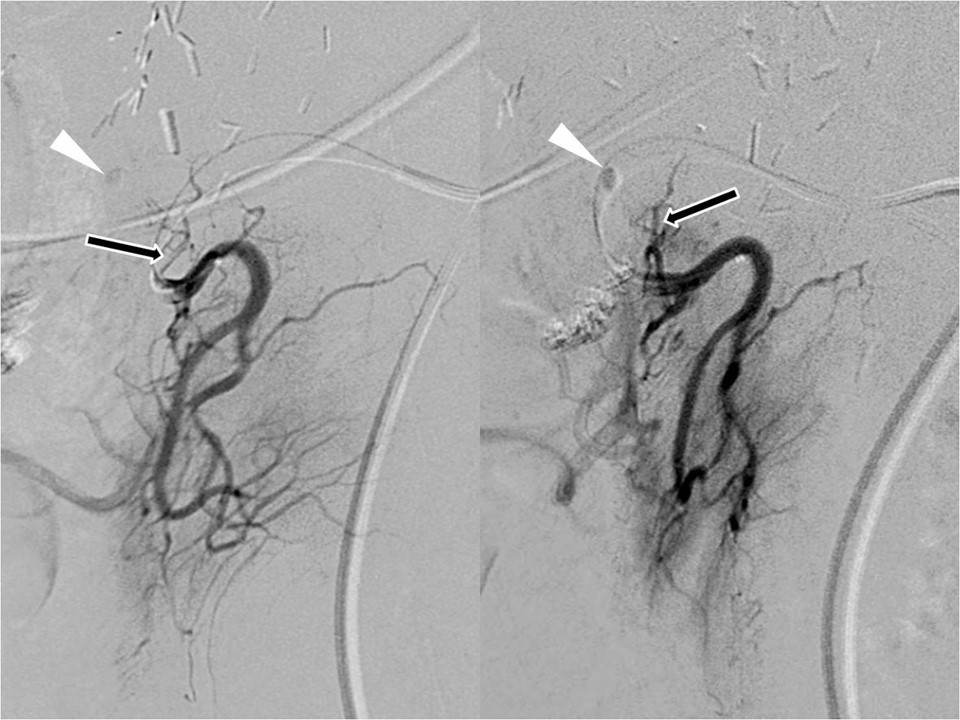

복강동맥조영술을 시행하였을 때 십이지장 구부 부근에 작은 거짓동맥류가 보였으나 정확한 영양동맥은 구분하기 어려웠음(Fig. 1). 위십이지장동맥에서 처음 기시하는 췌십이지장동맥의 선택적 동맥조영술에서 췌십이지장동맥의 최근위부에서 예각으로 기시하는 분지로부터 십이지장 구부의 거짓동맥류가 조영되었음(Fig. 2).

Fig. 2.

Selective pancreaticoduodenal arteriograms confirm that the feeding artery of the pseudoaneurysm (arrowhead) is the first branch (arrow) of the pancreaticoduodenal artery. But, the feeding artery arises from the parent artery with acute angle.